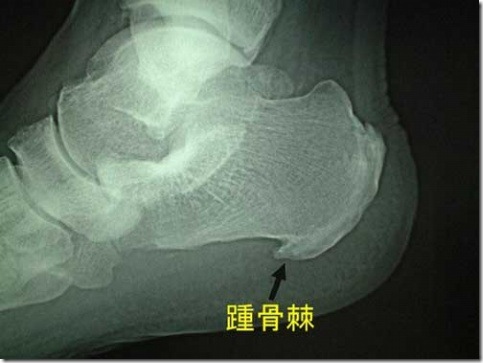

clip_image003

跟骨骨刺的有无,通常使用X光照片可以明确。

对于跟骨刺的形成,过去认为是由于长期行走和长时间站立而引起的退行性病变,但这一理论对很多因骨质增生而产生的临床表现无法做出确切的解释。最近的理论是“足部力学的动态平衡失调",造成跖长韧带,跖筋膜挛缩,引起跟骨附着点处持续性的牵拉损伤,韧带与筋膜的纤维就会不断地被撕裂,与此同时人体自身就会通过代偿机制的保护作用,把大量钙与磷输送到被撕裂的韧带与筋膜的附着点处,以加强韧带和筋膜的附着点处不被拉伤或拉脱,久而久之这些大量聚集的钙质与磷会使韧带与筋膜附着点钙化骨化,从而产生足跟骨骨刺这一病理现象。

足跟出现疼痛与跟骨骨刺有一定关系,但并非完全由跟骨骨刺引起。赵幼林医师观察了229例病人,经照片证明有跟骨刺的顽固性跟痛症患者中,110例单足痛,但两侧均有骨刺;14例双足痛,仅单侧有骨刺;10例骨刺发生于无痛侧。

早在1915年,就有人认为跟跖侧痛与跟骨骨刺有关,但它们间的确切关系目前仍不十分清楚。在跟跖侧痛患者中,约50%的患者有跟骨骨刺存在,但许多有跟骨骨刺的人并无跟跖痛。Shmokler观察发现在有跟骨骨刺的人群中,仅5.2%发生过跟跖侧痛。Tanz观察100例无跟痛的患者,发现有16%的患者有跟骨骨刺跟骨骨刺仅是一个X线片表现,可能源于跖筋膜等劳损引起的慢性炎症。跟跖侧疼痛的程度与骨刺大小不成正比,绝大多数骨刺并无疼痛。

另外说明一下,在最新的《足踝外科学》中,没有单独把跟骨骨刺作为病种来看待,只是一个病理现象。